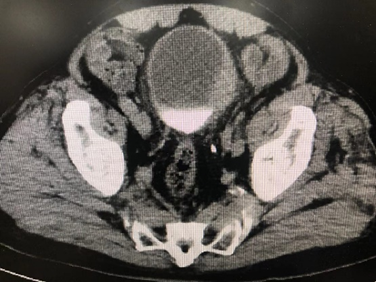

病例四,76岁男性,膀胱肿瘤电切术后2个月,复查CTU提示膀胱癌复发可能,左侧壁不均匀增厚,范围约4cm,尿液TCT+特殊染色提示高级别尿路上皮癌细胞阳性,外院病理切片于本院会诊提示高级别尿路上皮癌(G3),可见广泛固有层侵犯,局灶侵犯固有肌层。行机器人辅助腹腔镜膀胱根治性切除术,盆腔淋巴结清扫术,原位膀胱术,术者:王国良教授。